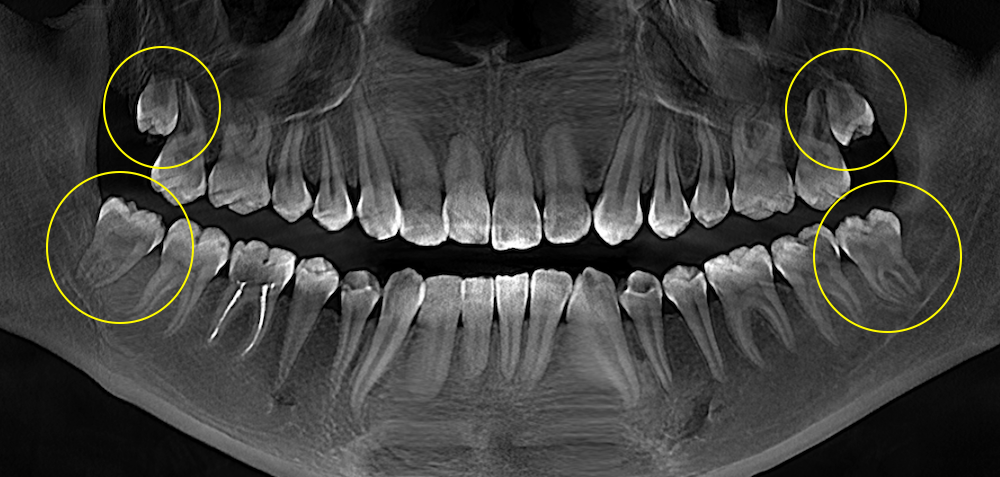

Під час огляду та рентгенологічної діагностики лікарка побачила всі чотири зуби мудрості. Вони ще не були повністю сформовані, але вже мали положення, яке потенційно могло ускладнювати ортодонтичне лікування і вимагало окремої оцінки перед початком лікування.

- На верхній щелепі зуби мудрості ще були на ранній стадії розвитку: коронкова частина вже сформувалась, а корені ще ні.

- На нижній щелепі корені вже формувались активніше, але ще не були повністю завершені.

Саме такий період часто є більш сприятливим для видалення: зуб уже можна чітко визначити на знімку, але корені ще не стали довгими й складними за формою. Це може зробити втручання менш травматичним і більш прогнозованим.